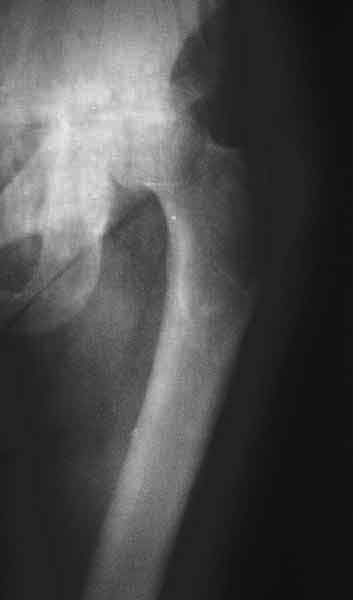

Насчет 8 см согласен с А.Н. Челноковым, это наверное ортопедическое за счет приводящей, сгибательной контрактуры и, возможно, колена. на ликвидацию укорочения у нас обычно уходит около 2-х нед. снимки в приложении, возможно не очень показательные, но других с ходу не нашел, завтра еще поищу.

Еще пара фото, ситуация несколько иная, задачи те же, открытое вправление застарелого вывиха в 2002, молодой возраст. Сейчас госпитализирована для эндопротезирования.